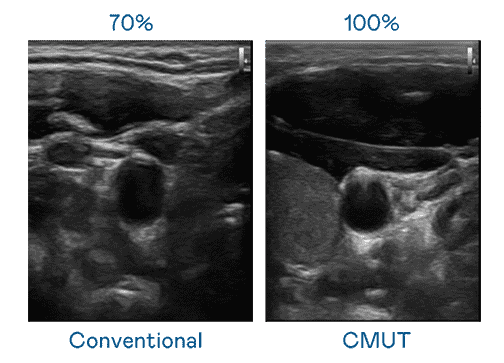

CMUT 技术是一种用电容式微机电元件来产生超音波讯号的技术。。。与传统 PZT 压电式技术相比,,,CMUT 频宽增加 30%,,,更宽频的超音波讯号让影像解析度大幅提升,,,,是实现高影像品质医疗超音波扫描、、促进精准医疗发展的关键技术。。。

超音波影像的解析度高低,,,,首先取决于探头能发出的讯号频宽。。。。www.z6.com CMUT 可提供高清晰的超音波讯号,,,,提供高频宽、、高灵敏度、、、、影像纹理细节更高的超音波影像,,,协助医护人员缩短影像判读时间及利用精准的医疗影像进行诊断。。。。